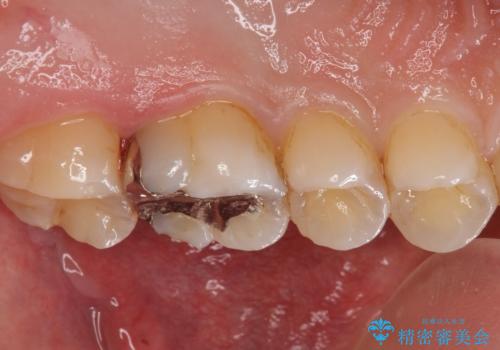

コンタクトカリエスの治療

- 虫歯の検査のために来院された患者さまです。

レントゲンで診査したら、歯と歯の間に虫歯(コンタクトカリエス)が見られたので

e-maxインレーで治療を行いました。

コンタクトカリエスは歯ブラシでは磨くことはできないため、虫歯になりやすい箇所の一つです。

毎日のフロスを行うことでコンタクトカリエスを防ぐ事ができます。